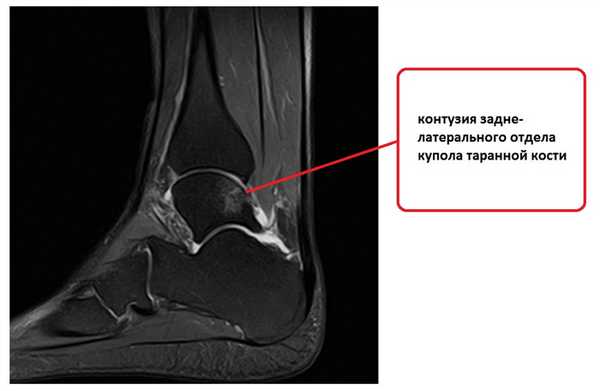

При выполнении стресс рентгенограмм определяется выраженная латеральная нестабильность голеностопного сустава.

Для подтверждения механической нестабильности выполнены стресс-рентгенограммы голеностопного сустава с «варус-стресс тестом» и «тестом переднего выдвижного ящика». Критериями для постановки диагноза нестабильности является ангуляция таранной кости в коронарной плоскости более 4 градусов и смещение таранной кости кпереди в сагиттальной плоскости на 4 мм, или разница с контрлатеральной стороной в 2 градуса и 2 мм соответственно.

Если с варус-стресс тестом всё очень наглядно, оценивать передний выдвижной ящик рентгенологически чуть сложнее. Для этого можно либо обозначить центр купола таранной кости и встречной суставной поверхности большеберцовой кости точками и сравнивать расстояние между ними с или без нагрузки в задне-переднем направлении, либо использовать в качестве вспомогательного ориентира тень медиальной лодыжки и расстояние от неё до начала шейки таранной кости.